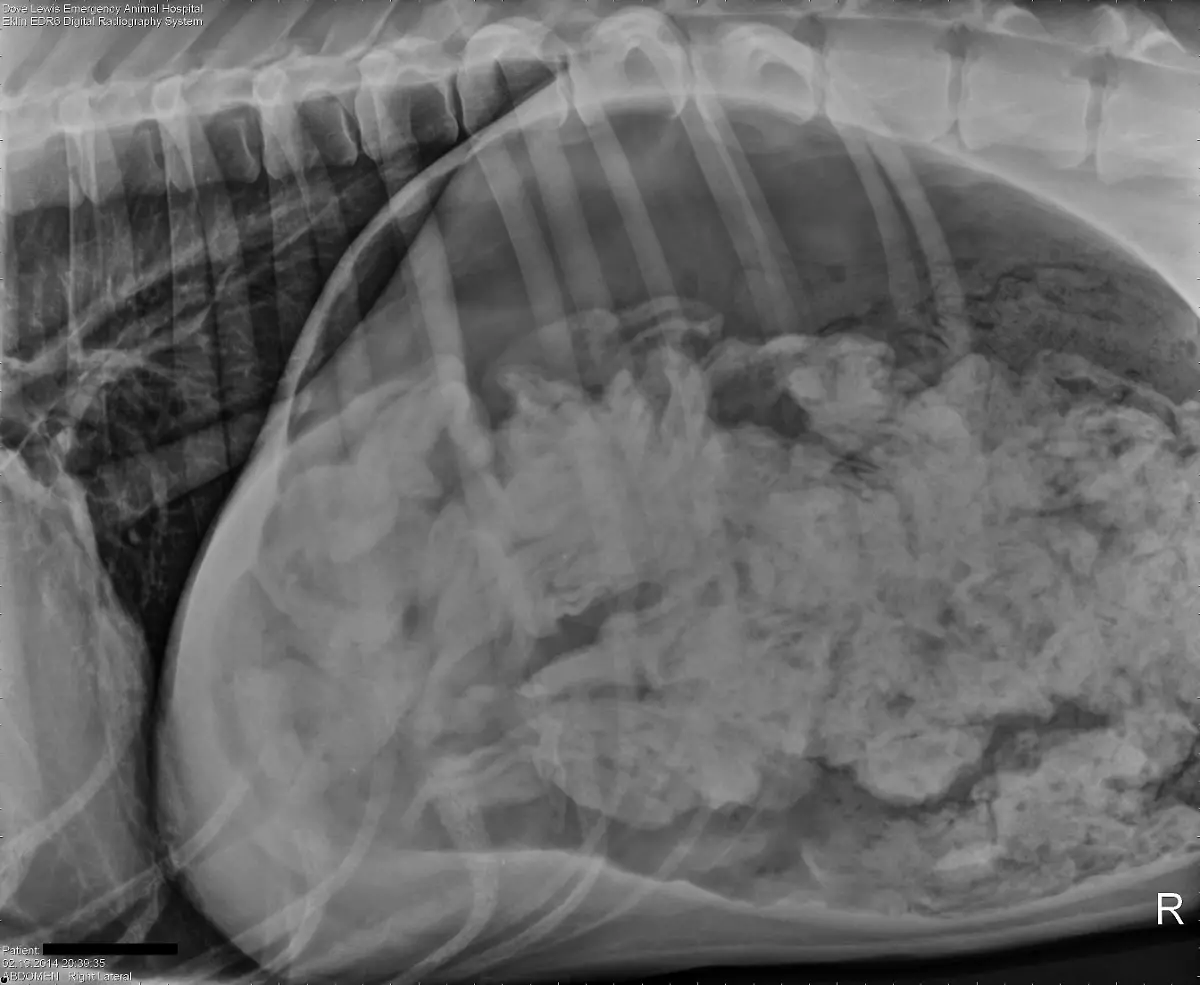

Socken, Kieselsteine, Außerirdische - Röntgenbilder von Mägen US-amerikanischer Haustiere zeigen die skurrilsten Gegenstände. Eine Zeitschrift zeichnet jedes Jahr die außergewöhnlichsten Aufnahmen aus.